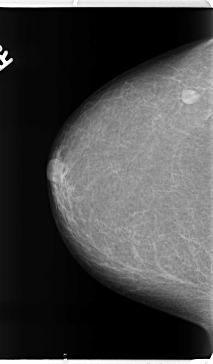

B_3153_1.RIGHT_CC

RIGHT_CC LINES 4728 PIXELS_PER_LINE 2760 BITS_PER_PIXEL 12 RESOLUTION 50 NON_OVERLAY